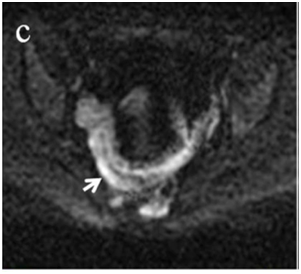

Figure 5 Comparison of coronal (a) and axial (c) DWI sequences with the respective

after contrast medium injection (b, d).